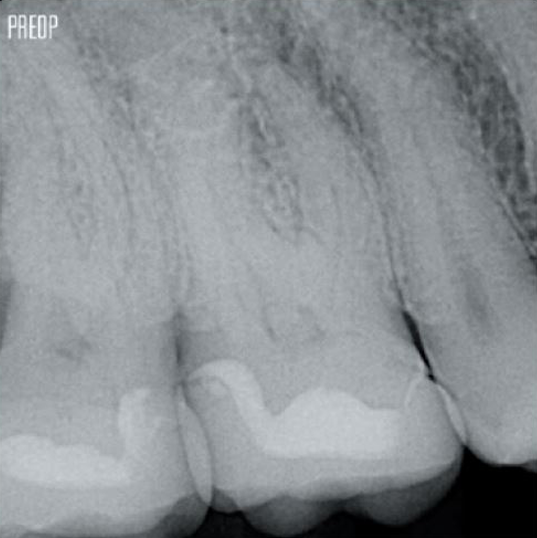

Fotos cortesia do Dr. Ahmed Salman

O tratamento bem-sucedido do canal radicular começa com o acesso adequado à câmara pulpar. O procedimento ideal fornece acesso aos orifícios do canal radicular com perda mínima de dentina.

Uma cavidade endodôntica conservadora (CEC) é recomendada com o sistema TruNatomy®.

A união da geometria da lima, as conicidades regressivas e o fio fino e altamente flexível permitem um tratamento eficiente do canal radicular, removendo a dentina apenas onde for clinicamente necessário.1